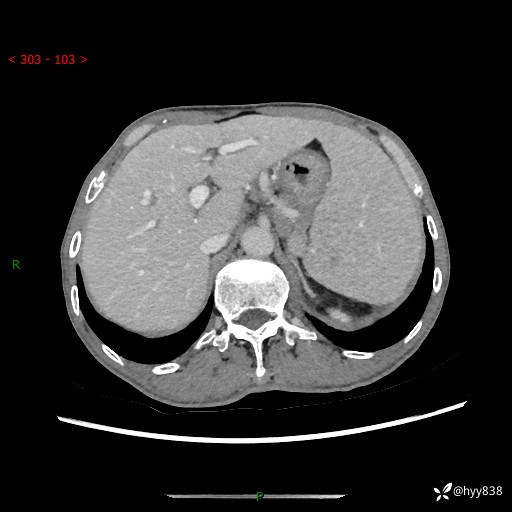

老年男性,脾大并脾脏弥漫粟粒状低密度,淋巴瘤 VS 肉芽肿 VS 血管瘤---结果公布

简要病史: 患者于3月前无明显诱因出现脾大,伴腹部轻微不适,具体不详,无腹痛、腹泻、腹胀,无头晕、头痛、乏力,无恶心、呕吐、呕血,无胸闷、气短、胸痛不适

上腹部CT平扫+增强